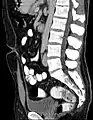

A tomografia computadorizada (reconstrução sagital) que mostra o Úraco achado incidental em um homem de 44 anos de idade, a trajetória se move para frente e para cima a partir da bexiga para o umbigo na linha média.